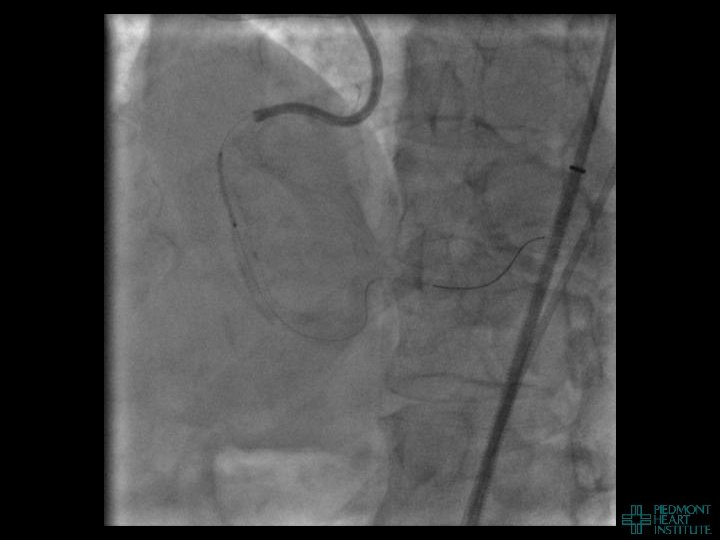

Coronary Perforation Methods of Patient Management • Dual Catheter (‘Ping Pong’) Technique • Prolonged

Coronary Perforation Methods of Patient Management • Dual Catheter (‘Ping Pong’) Technique • Prolonged balloon inflation and covered stents • Reversal of anticoagulation — Know contradictions to protamine sulfate for UFH; Avoid bivalirudin, LMWH — Reserve GP 2 b 3 a inhibition until successful crossing and wire change-out Embolization • — Coil, gelfoam, methacrylate, autologous blood/fat • Microcatheter Occlusion • Confirmation of successful management — Contralateral injection — Right heart catheterization — Echocardiogram — Contrast echocardiography